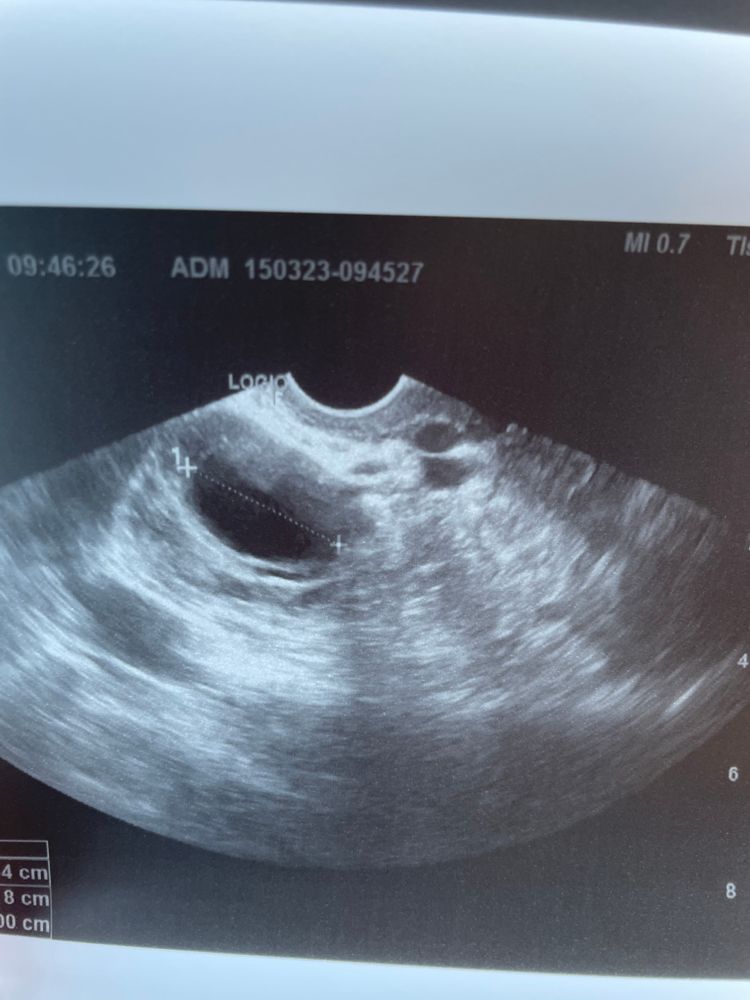

Фолликул или киста ЖТ?

На узи жидкость , но врач так и не сказала что это, фолликул так вырос или киста желтого тела?!

Фолликул в понедельник был 18 мм. Был ПА, после чего заболел живот (возможно овуляция, обычно ее чувствую ) .А сегодня, в среду уже что-то размером 26 мм.

фото прикрепляю

Спорно что это по фото. Кровоток надо смотреть. Если есть, то это ЖТ. Если его нет, то фолликул.

Но вообще размер слишком большой для желтого тела, если овуляция была вчера-позавчера.

я склоняюсь к тому, что раз жидкость уже есть в позадиматочном пространстве, значит скорее всего овуляция вот-вот будет. Или происходит в данный момент.

а по фото узи похоже, что ЖТ, т.к. края неровные. Фолликул обычно с четкими краями

Евгения , даже если это фолликул, меня смущает размер. Может ли он вырасти за 48 часов на 8 мм? Такое вообще бывает ?